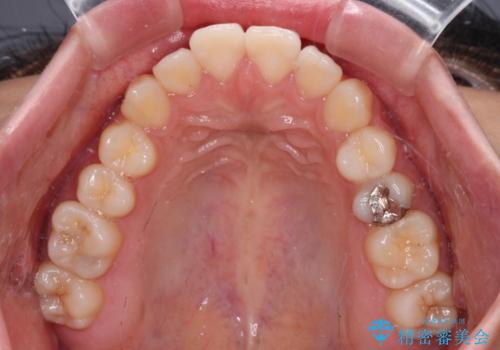

横顔の印象を変えたい ワイヤー装置での抜歯矯正

- 口元の突出感と上下前歯のズレを気にして来院された患者様です。

舌の突出癖により上下の前歯は非接触となっている状態でした。

舌のトレーニングを行わないと上下前歯の接触達成は困難であるため、トレーニングをしっかりと行っていただきながら、治療を進めて行くこととしました。

突出感改善のため、上下左右の第一小臼歯4本を抜歯し、ワイヤー装置にて矯正治療を行うこととしました。

舌のトレーニングをしっかりと行ってくださり、予定通りの期間で理想的な仕上がりを達成することができました。